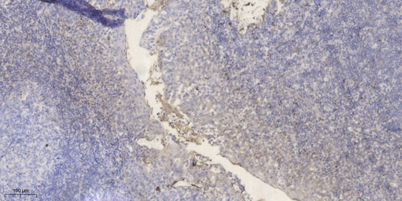

Product name: PRSS33 rabbit pAb

Dilutions: Western Blot: 1/500 - 1/2000. Immunohistochemistry: 1/100 - 1/300. ELISA: 1/10000. Not yet tested in other applications.

Background: function:Serine protease that has amidolytic activity, cleaving its substrates before Arg residues.,induction:Up-regulated by phorbol ester PMA.,similarity:Belongs to the peptidase S1 family.,similarity:Contains 1 peptidase S1 domain.,tissue specificity:Predominantly expressed in macrophages. Present in the spleen, small and large intestine, lung and brain (at protein level). Highly expressed in peripheral leukocytes, ovary, retina, spleen and stomach. Moderately expressed in thymus, uterus and platelets, as well as some brain tissues, such as thalamus and fetal brain.,